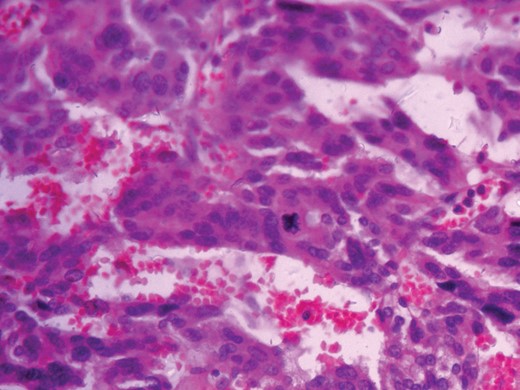

Histopathological analysis reported a well-encapsulated cellular lesion composed of sheets, cords and trabeculae of round to oval epithelial cells with abundant eosinophilic cytoplasm and vesicular nuclei showing Grade 1–2 pleomorphism. Foci of bizarre-looking cells with frequent mitotic figures (1–2/10 HPF) seen. Focal areas of capsular invasion were seen without vascular invasion. A histopathological study indicated ACC (Figs 7 and 8).